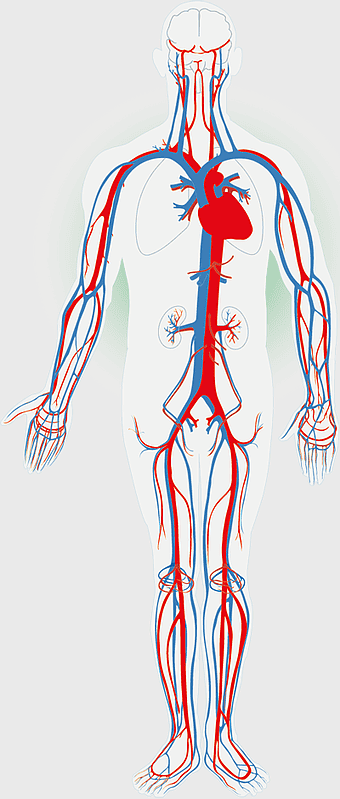

human circulatory system, blood vessel anatomy, weight loss exercise benefits, heart and artery health, vascular network visualization, cardiovascular health illustration, systemic circulation diagram -

circulatory system diagram, human cardiovascular anatomy, blood vessel network, heart circulation, systemic circulation, venous system, arterial pathways -